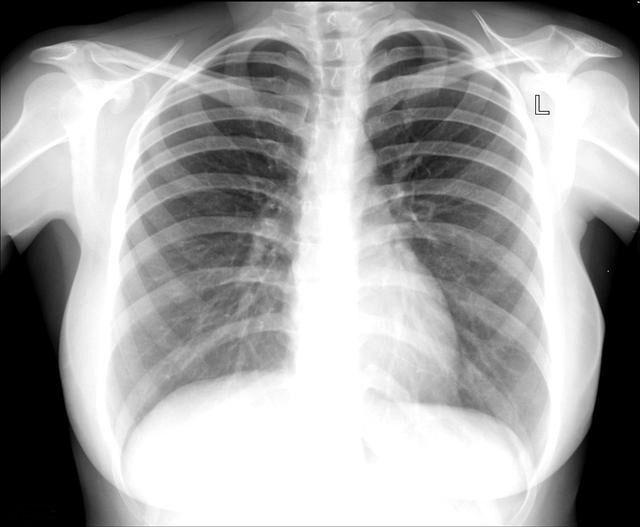

胸片是重要的肺部检查项目之一,可以说是呼吸科医生的眼睛,在没有胸片之前的时代,肺部的病灶都是无法准确测量和观察其密度以及周边情况的,有了胸片很多疾病才得以准确的诊治,但胸片有其局限性,由于是使用二维看三维结构,形如将人拍扁印在一张纸上,所以病灶会受到周围组织阴影的干扰,甚至遮掩,比如心脏后面肺组织产生病灶有可能看不到,所以胸片看上去没有问题并不能完全排除肺部疾病的可能性。

因此,检查类似于肿瘤这样的恶性疾病,不适合仅使用胸片,最好结合胸部CT来看,胸部CT的原理相当于将人体切片并一片一片的观察, 肺部上下前后的病灶都一览无遗,1mm以上的病灶基本上不会遗漏,尤其是1cm以下在胸片上看不出来的病灶在CT上可以明显看出来。